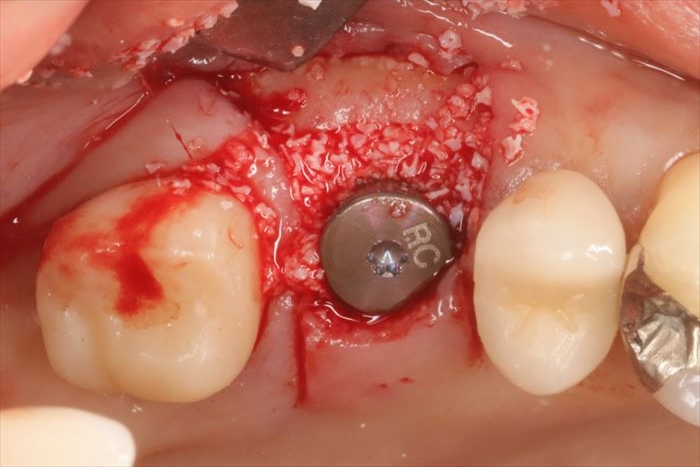

ストローマンインプラントの埋入を終えました。

歯ぐきの形態を形成するためのヒーリングキャップを締結し、周囲の骨欠損部分に骨移植材を填入し骨増生します。